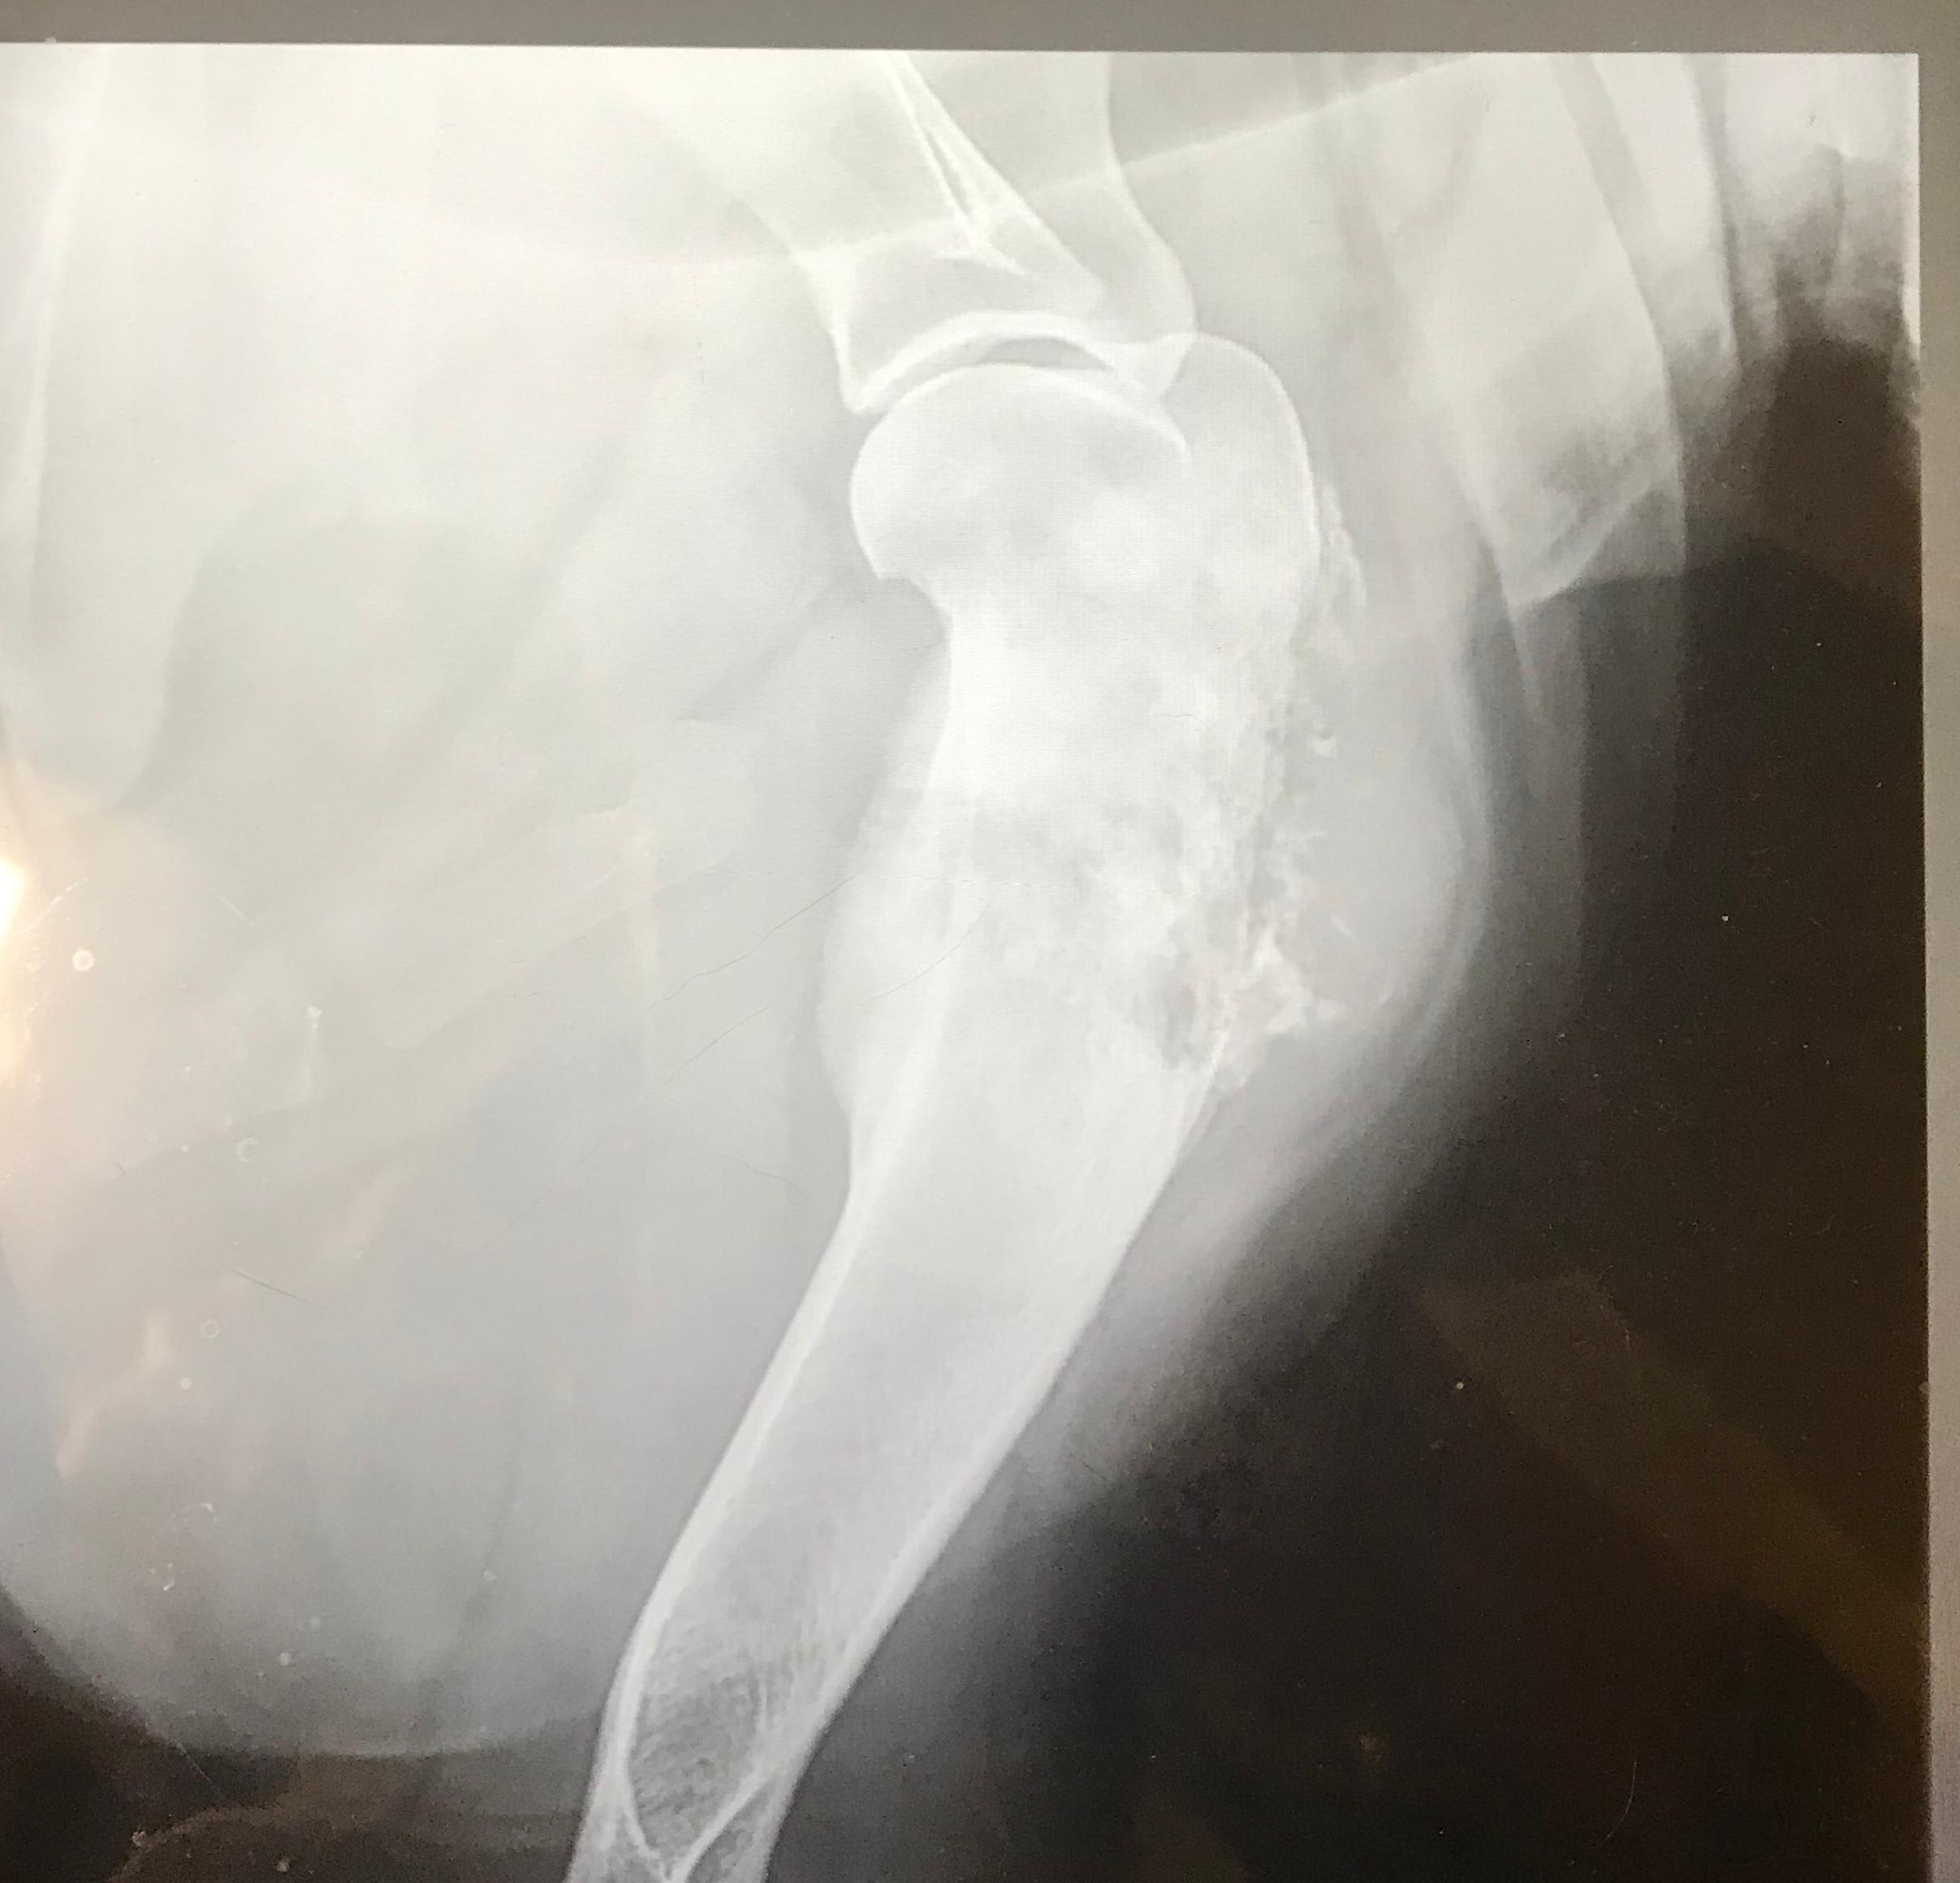

Male neutered 160lbs 3-4years old X-ray of right front leg What is wrong with my dog’s leg?

Hello and thank you for reaching out about your dog. These xrays are very concerning for either a fungal infection (very much dependent on where you are living) or a bone cancer (osteosarcoma). These xrays I am sure have also been evaluated by your veterinarian and hopefully a radiologist as well. I would recommend chest xrays to look for cancer metastasis or diffuse fungal infection and you may need to have your veterinarian perform a bone core biopsy for a diagnosis. This is usually very painful and your dog should be on good pain meds and rest during this time. Treatment options are very different for bone cancer vs. fungal infection so a proper diagnosis is extremely important. Best of luck!